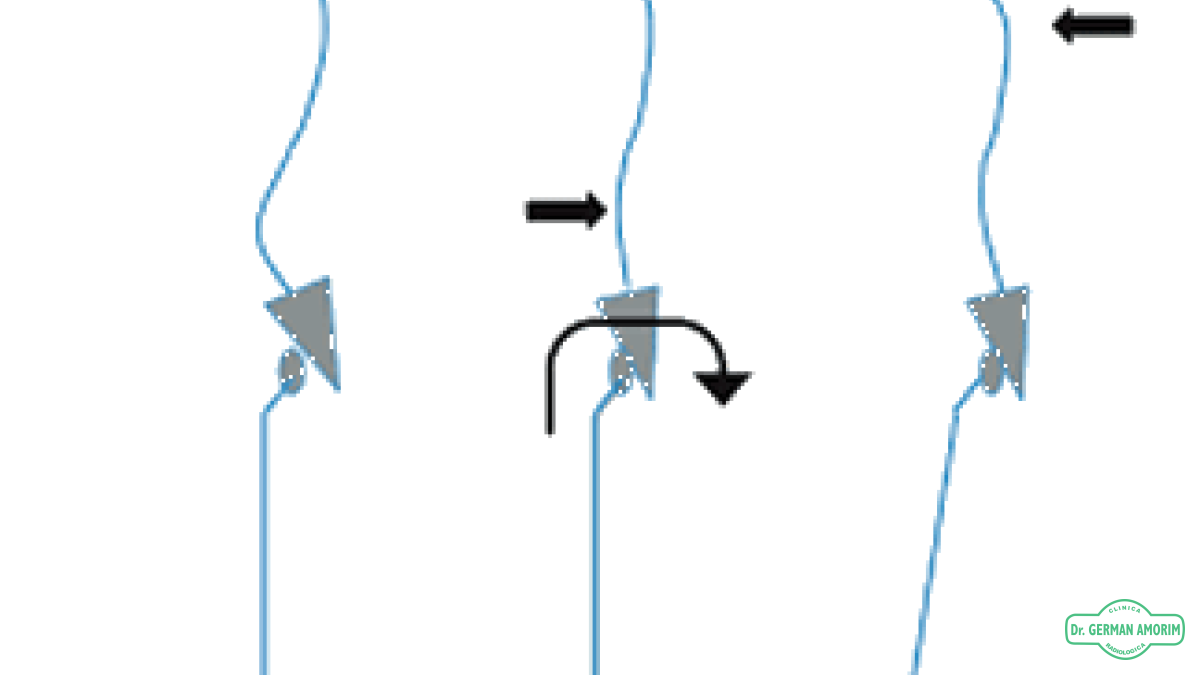

Este sencillo estudio radiográfico nos permite visualizar y evaluar la alineación de todas las vértebras, las que deben estar siempre bien alineadas desde arriba hacia abajo, (igual a como cae el hilo de la plomada del albañil).

En la visión de frente y en la visión de perfil se controlan las curvaturas que deben ser cervical y lumbar en lordosis (concavidad posterior) y dorsal y lumbar en cifosis (concavidad anterior).

Es pedido por el profesional médico frecuentemente para pacientes traumatológicos con diagnósticos por ejemplo de escoliosis, acortamiento de miembros inferiores, etc.